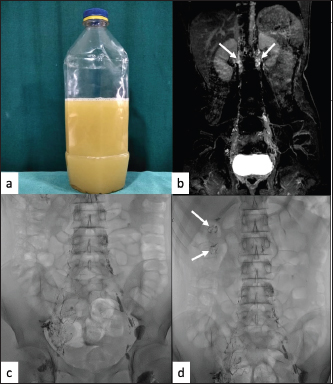

A 15-year-old male presented with a complaint of the intermittent passage of milky urine (Figure 1a) of 1-year duration associated with weight loss of 8 to 9 kg. There was no history of fever or abdominal pain. No history of trauma, surgery, hospitalisation, contact history with a tuberculosis patient or urinary infection was present. General physical examination was normal with no facial or limb edema noted. Urine biochemical examination revealed the presence of triglycerides and chylomicrons, which suggested chyle in urine. All other investigations including urine for protein, microfilarial antigen test, malarial antigen test, etc were within normal limits.

Dynamic contrast magnetic resonance lymphangiography (DCMRL) showed opacification of pelvic as well as bilateral retroperitoneal lymphatic channels (Figure 1b), but no definite communication with pelvicalyceal lymphatics was identified.

For further evaluation, CLL was performed by direct intranodal injection of total of 10 ml of lipiodol (iodinated ethyl ester of fatty acids of poppy seed oil) into bilateral inguinal lymph nodes under digital subtraction angiography (DSA) machine. On the right side, multiple distorted lymphatic channels were opacified in groin and pelvis without opacification of interval lymph nodal stations (Figure 1c). After 40–45 minutes of intermittent fluoroscopy, a few abnormal lymphatics were seen in the right renal region (Figure 1d).

Figure 1. (a) Sample of patient’s urine showing gross chyluria. (b) DCMRL coronal image showing bilateral paravertebral lymphatic channels (arrows). (c) CLL image showing multiple ill-defined channels in the right inguinal and hemi pelvis. Normal lymphatic channels and lymph nodes are seen on the left side. (d) CLL image showing lipiodol pooling in the right renal area taking the shape of calyces (arrows).